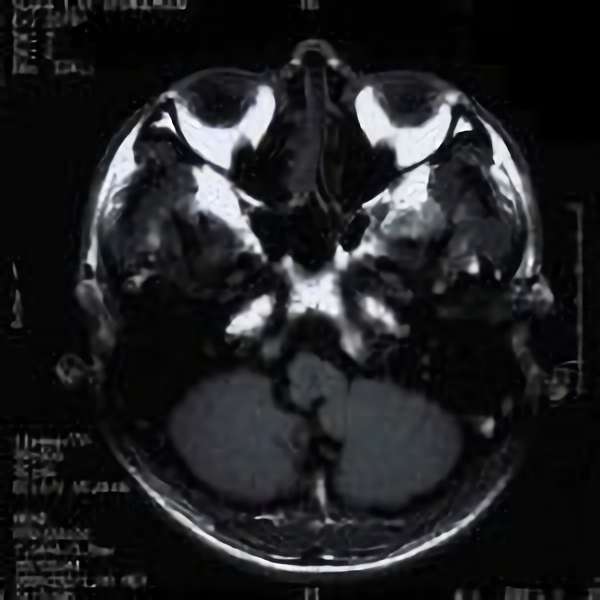

'19年5月

30代

富永/久貝

右中小脳脚 出血再発

SM 3(S1,E1,V1)

米国の病院

No.359 モニタリング

No.359 手術前

No.359 手術中

No.359 手術後

出血既往があり。2回の手術前血管内手術の後に、

Lateral transpeduncular approachにより再々出血予防を目的に

摘出手術を行う。完全摘出であることを確認した。

手術による合併症や後遺症なしで退院した。経過良好。